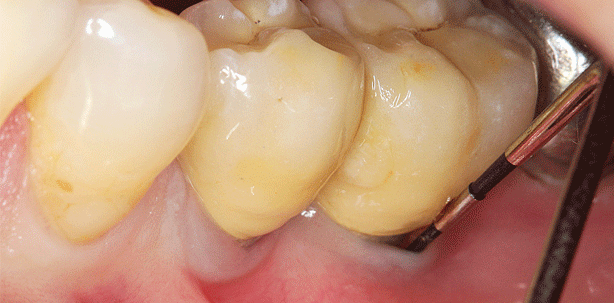

Die Zahnzwischenraumpflege gestaltet sich jedoch in der Regel schwierig. Die Handhabung von Zahnseide oder Interdentalbürsten erfolgt gerade im Seitenzahnbereich meistens ohne direkte Sicht auf die zu reinigende Zahnfläche und ist somit recht kompliziert, zeitintensiv und im Ergebnis nicht kontrollierbar. Dementsprechend gering ist die Akzeptanz in der Bevölkerung, sodass insbesondere Zahnseide im Rahmen der täglichen Mundhygiene nach wie vor selten oder gar nicht verwendet wird.

Eine effektive Interdentalraumhygiene wird leider in den meisten Fällen nach wie vor nicht zufriedenstellend erreicht. Kommt eine supra- oder gar infraalveoläre Taschensituation hinzu, ist eine ausreichende Plaqueentfernung aus solchen Bereichen im Rahmen der heimischen Mundhygiene hoffnungslos.

Pulverstrahlgeräte sind bereits seit vielen Jahren im Rahmen der supragingivalen Anwendung insbesondere bei der professionellen Zahnreinigung erfolgreich im Einsatz. Die Indikationserweiterung auf subgingivale mit Biofilmen belastete Implantatoberflächen wurde mithilfe eines nur wenig abrasiven und löslichen Glyzin-Pulvers (z.B. Air-Flow Powder Perio, EMS, Nyon, Schweiz) und speziellen Applikatoren möglich (siehe Abbildungen 4, 5 und 7). Die Reinigungs- bzw. Dekontaminationswirkung an Implantatoberflächen dieser (ca. 20 μm großen) aus der Aminosäure Glyzin bestehenden Kristalle ist erheblich besser im Vergleich zu konventionellen Handinstrumenten und Ultraschallscalern.28–31 Seit Kurzem ist ein glyzinbasierendes Pulver erhältlich, welchem Chlorhexidin beigemengt wurde (Air-Flow Powder Plus, EMS). Es bleibt jedoch abzuwarten, ob damit eine klinisch relevante Verbesserung der Dekontaminationsleistung erzielt werden kann.

Unabhängig davon konnte gezeigt werden, dass das Glyzin-Pulver im Rahmen des Strahlverfahrens keine nachteiligen Effekte auf das umgebende Weichgewebe ausübte. Im Vergleich hierzu führten konventionelle Handinstrumente zu einer erheblichen Traumatisierung der angrenzenden Weichgewebe.23, 32